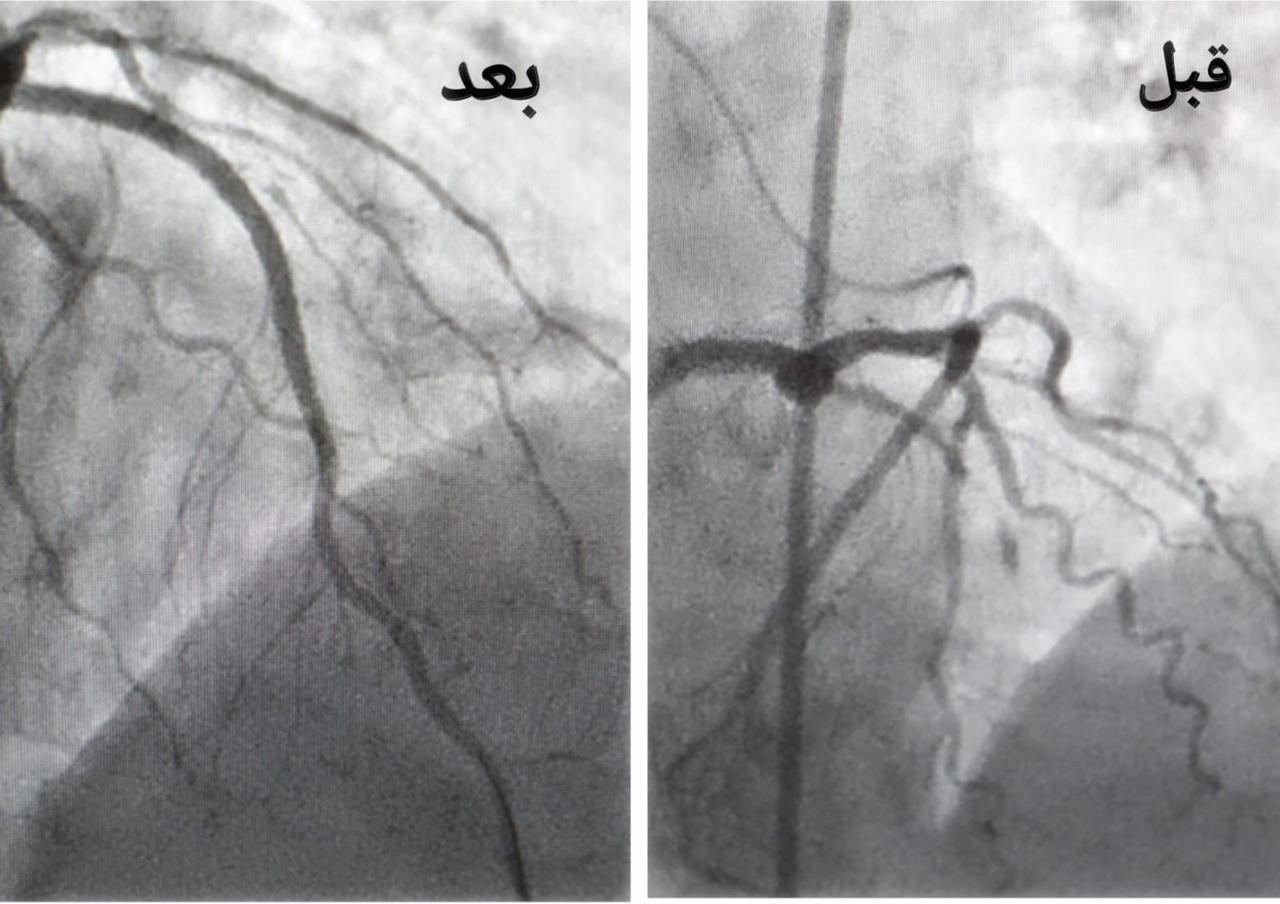

وأكدت الصحة في جدة أن الفرق الطبية بمجمع الملك عبدالله الطبي تمكنوا بفضل الله من إنقاذ حياة الحاجة حيث تعرضت لذبحة صدرية غير مستقرة و جلطة قلبية حادة، كادت أن تودي بحياتها بعد انتهاء مناسك الحج وأثناء مغادرتها المملكة، حيث أحضرت إلى قسم الطوارئ وتم تقديم الخدمات الإسعافيه الأولية لها و نظراً لوضع حالتها الصحية الحرجة نقلت على الفور إلى غرفة العمليات لعمل القسطرة القلبية العاجلة، وتم فيها فتح الشريان الأمامي النازل و تركيب دعامات دوائية في أقل من 70 دقيقة من وصولها للمجمع الطبي ليتم نقلها لقسم العناية المركزة ومتابعة الحالة لحين استقرارها وخروجها من المستشفى ومغادرتها المملكة.

وأضافت أن الفرق الطبية أسهمت أيضاً في إنقاذ حياة حاج بنجلاديشي تعرض لجلطة قلبية حادة وأظهرت الفحوصات الطبية التي أُجريت له إصابته بجلطة حادة في عضلة القلب مع وجود انسداد كامل في الشريان الأيمن التاجي، و لخطورة الحالة تم إجراء عملية قسطرة علاجية عاجلة تم فيها فتح الشريان الأيمن وتوسيعه، ليتم متابعة الحالة مع الفرق الطبية والتمريضية لحين استقرار الحالة وخروجها ومغادرة أرض الوطن بالسلامة.